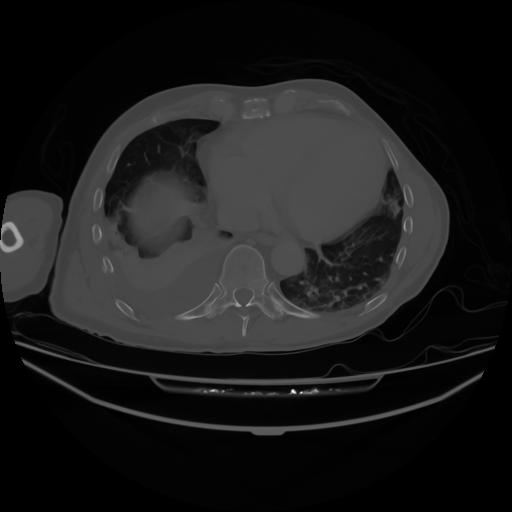

4 CUERPO,CE,Axial,3.0,CUERPO,,